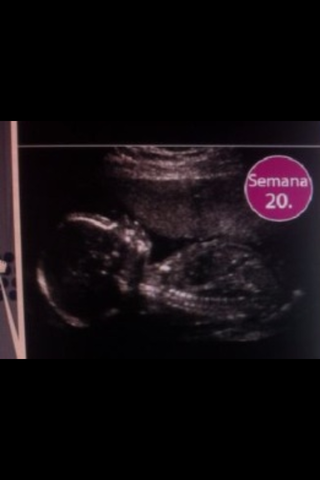

Él bebe ya puede oír los latidos del corazón de la madre

Si él bebe es una niña ya tendrá en sus ovarios huevos primitivos

Su cerebro está desarrollando sus sentidos del gusto, tacto, olfato, audición, visión y tacto

Ya se puede saber el sexo del bebe

Sus medidas son 20 cm y 340g

Las uñas, parpados y cejas son visibles, solo faltan las pestañas

El sistema límbico del bebé esta en desarrollo,se encargan de sentimientos y emociones